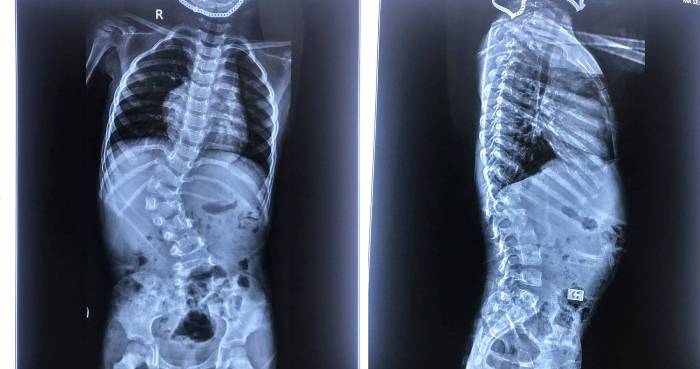

![]() |

| Phim chụp sau phẫu thuật chỉnh vẹo cột sống |

Bác sĩ Khánh cho biết, lúc các con tắm là lúc dễ dàng phát hiện các dấu hiệu vẹo cột sống nhất nhất nhưng các con thường xấu hổ, không cho bố mẹ quan sát. Bởi vậy các phụ huynh cần quan sát những dấu hiệu như mất cân bằng hai vai, mất cân bằng khung chậu, vai lệch, vai gồ, eo lệch, dánh nghiêng… để đưa ngay con đi khám và điều trị, tránh lỡ mất thời gian vàng chữa trị sớm khiến các con phải mổ.